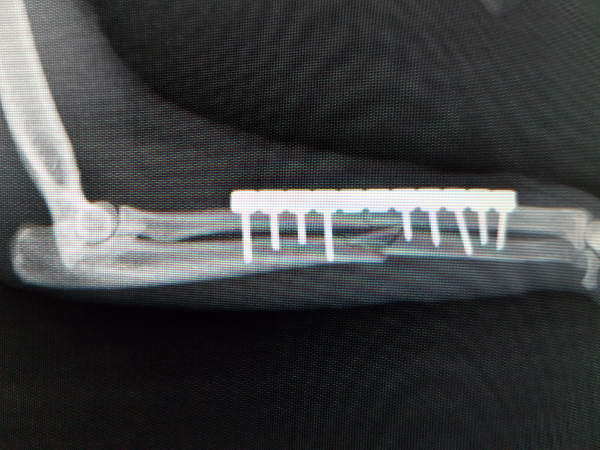

Con más de 20 años de experiencia en éste campo, el Dr. Esteban Spínola, Veterinario Jefe del Hospital Veterinario Atabal, está apuntado a dicha carrera desarrollando y actualizándose constantemente en las diferentes técnicas que esta especialidad exige.

Para ello, asiste a importantes y numerosos Congresos Nacionales e Internacionales y a los Grupos de Trabajo de Traumatología del Gevo de Avepa (Asociación de Veterinarios Especialistas en Pequeños Animales), de la que es miembro.